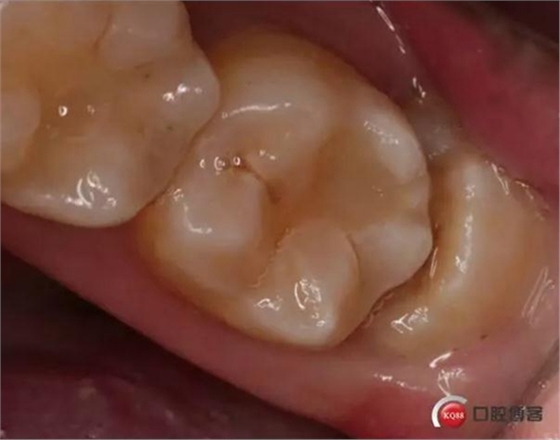

檢查:口內(nèi)可見38未完全萌出,無松動(dòng),周圍牙齦顏色正常,叩診(—)觸診(—),X線顯示近中阻生,雙根